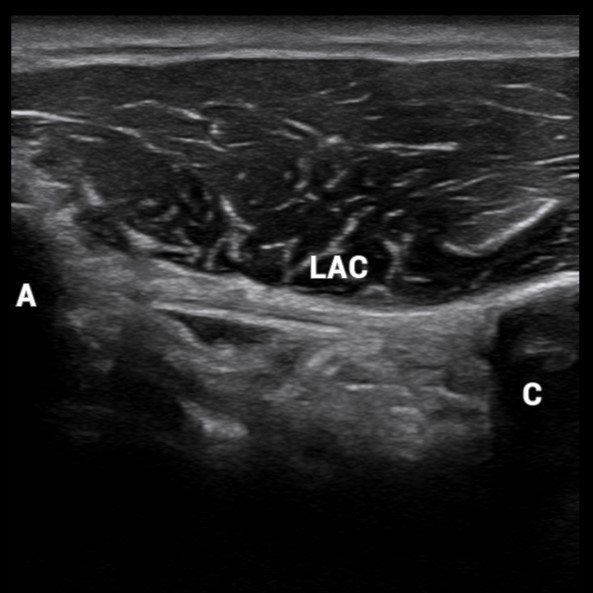

Ecografía

Precisión mediante ecografía